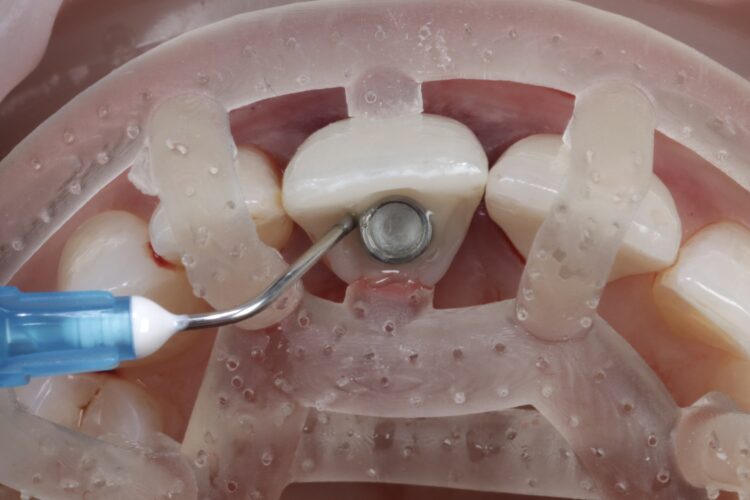

The surgical guide was checked in the mouth, ensuring it was fully seating and not in contact with the adjacent teeth.

The standard CONELOG® (BioHorizons Camlog) guided drill sequence was followed. The Guided Surgical Kit is very simple to use with a streamlined number of drills. The CONELOG® drills support primary stability, with side-cutting features and apical threads that engage the native bone.

The CONELOG® Progressive-line implant maximised primary stability and in this case the implant was inserted at 70Ncm. The pre-made temporary was used as the temporary restoration; however, there would also be the option of modifying the existing crown.

The implant was placed in close contact with the palatal bone, 1mm below the buccal bone height. A temporary cylinder abutment was connected, with flowable composite placed to attach the temporary restoration. The composite resin was used to create the optimal emergence profile ensuring a highly polished restoration in the transition zone.